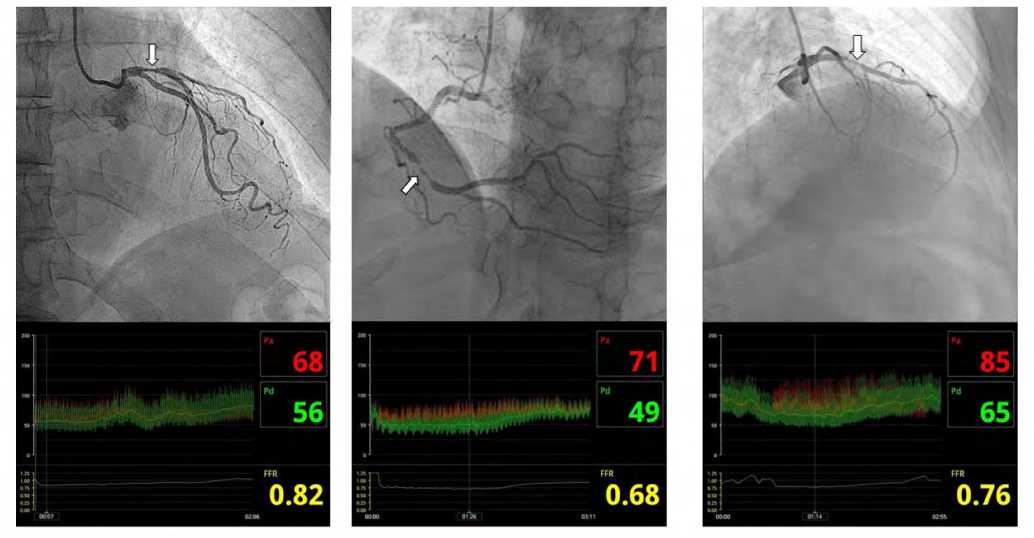

На рисунке 1 в качестве примера приведены три случая рентгеноконтрастной визуализации стенозов КА, для каждого из которых была выполнена процедура определения ФРК. Сравнение результатов ФРК с данными визуальной оценки степени стеноза демонстрирует диагностическую ценность гиперемического показателя. Действительно, в одном случае (рис. 1, крайний левый столбец) при ангиографически выраженном стенозе 75% определялся ФРК 0,82. То есть сужение КА лимитирует кровоток только на 18% от максимально возможного и является гемодинамически незначимым.

Напротив, для случая, изображенного в крайнем правом столбце на рисунке 1, ангиографически пограничный стеноз 30–50% почти в два раза больше лимитирует максимальный коронарный кровоток в сравнении с первым случаем (ФРК – 0,76 против 0,82) и является гемодинамически значимым. Пример в центре рисунка 1 иллюстрирует ситуацию, когда ангиографическая значимость стеноза совпадает с оценкой ФРК (стеноз 90%, ФРК – 0,68).

Рис. 1. Результаты ангиографического обследования с измерением фракционного резерва кровотока у пациентов с ишемической болезнью сердца (собственные результаты, пояснения в тексте)

Примечание: верхняя панель – данные коронарографии (аппарат Azurion 7, Philips, США), нижняя панель – данные ФРК (аппарат Volcano S5, Philips, США). Степень стенозов (указано стрелками) определялась по стандартной методике в проекциях (слева направо): LAO 0° CAUD 0°; LAO 30° CRAN 30°; RAO 30° CRAN 30°. Pa – давление крови в устье артерии, Pd – давление за стенозом, FFR – фракционный резерв кровотока.

Fig. 1. Results of an angiographic examination with measurement of FFR in patients with coronary artery disease (own results, explanations in the text) Note: the upper panel shows coronary angiography data (Azurion 7 system, Philips, USA), and the lower panel shows FFR data (Volcano S5 system, Philips, USA). The degree of stenosis (indicated by arrows) was assessed using the standard methodology in the following projections (from left to right): LAO 0° CAUD 0°; LAO 30° CRAN 30°; RAO 30° CRAN 30°. Pa represents aortic pressure, Pd denotes pressure distal to the stenosis, and FFR – for fractional flow reserve.